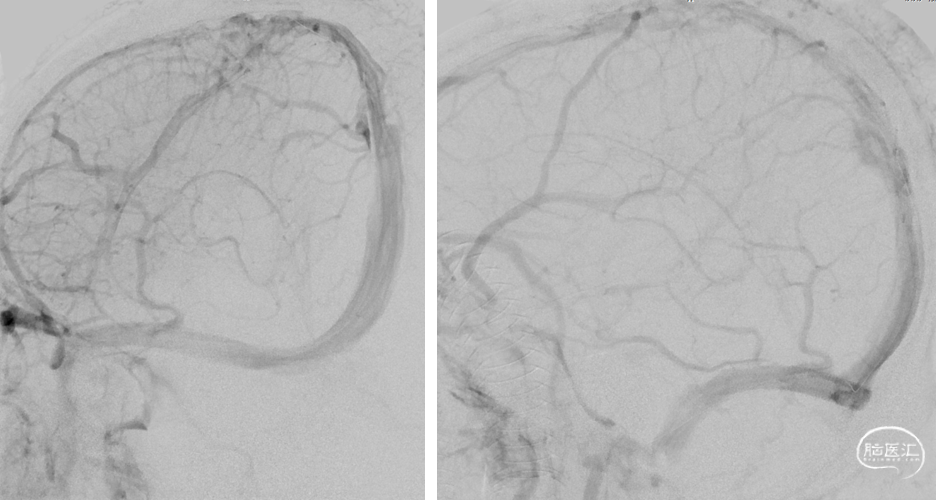

DSA(2022-1-6)

右侧颈总动脉造影示:上矢状窦显影模糊,右侧横窦、乙状窦未见显影,静脉回流缓慢。穿刺右侧颈静脉,留置8F血管鞘,全身肝素化,50万尿激酶入动脉滴注。

术前DSA